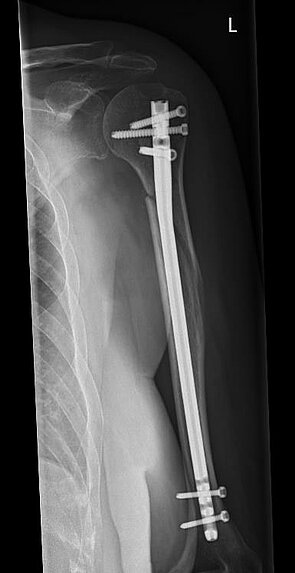

Während bei jüngeren Patienten die Rekonstruktion von Knochen und Gelenken im Vordergrund steht, führt bei älteren Patienten häufig der Gelenkersatz zur schnelleren Wiederherstellung der Beweglichkeit.